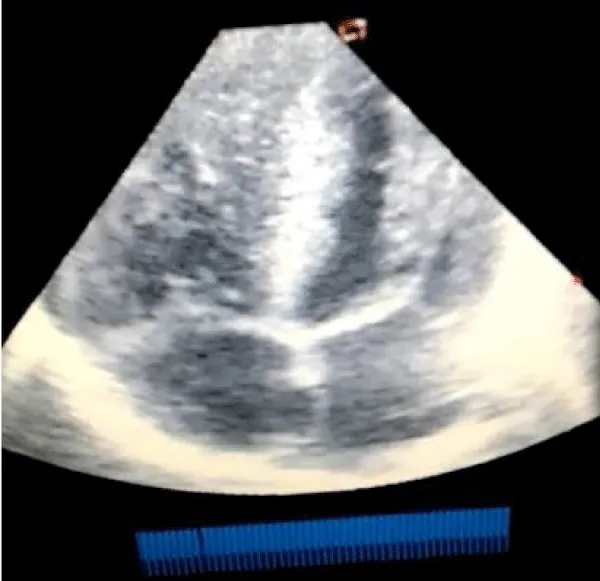

A male neonate delivered at term via SVD to a 24 years old G2P2 mother, who was diagnosed with gestational diabetes at 31 weeks of gestation who had poor glycemic control despite being on subcutaneous insulin and dietary modifications. Mother also had gestational diabetics during her first pregnancy (deranged glycated haemoglobin HbA1c) and claimed her blood sugar normalized after delivery. Her first child was a female and weighed 4.5 kg, alive and well and did not have any immediate neonatal complications. No family history of cardiac diseases. Birth weight of index baby was 4.8 kg (> 95% centile for age) and Apgar scores were 5/7/7 in 1, 5 and 10 minutes respectively. The physical examination showed a macrosomic infant (weight > 95% centile for age), thick upper extremity skin folds, broad shoulder and torso with a relatively smaller head, and plethoric look. He had respiratory distress with peripheral cyanosis. Oxygen saturation (SPO2) was 92% (room air) and urgent random blood sugar (RBS) was 4.6mmol/l. There were no other obvious malformations. Baby was admitted immediately after birth into the special care baby unit (SCBU) of a Federal Medical Centre in southern part of Nigeria for moderate birth asphyxia, severe respiratory distress and macrosomia. Child had persistent respiratory distress while on admission and further cardiac evaluation revealed displaced apex beat with no cardiac murmur. Chest x-ray done showed severe cardiomegaly with bi-ventricular and right atrial enlargements and a cardiothoracic ratio of 68% and oligaemia (Figure 1). Electrocardiography showed evidence of biventricular hypertrophy, right atrial enlargement, sinus tachycardia and occasional premature ventricular complexes (Figure 2). Echocardiography done on the 7th day of life showed severe bi-ventricular hypertrophy with significant narrowing of the left ventricular cavity, marked asymmetrical septal hypertrophy, moderate to severe dynamic subaortic stenosis (Peak gradient 45 mmHg) and left ventricular systolic and diastolic dysfunction (Figure 3). He was commenced on tabs propranolol at 1mg/kg/dose 8hrly and discharged after 5 days with improvement in respiratory distress. He also received oxygen therapy, intravenous fluid and intravenous antibiotics as well as intensive nursing care while on admission. Follow up echocardiography at 6 wks of life showed evidence of remarkable resolution of hypertrophy and improvement in ventricular function (Figure 4).

Download Image

Figure 4: Repeat Echocardiography at 6 weeks of life (apical 4 chamber view) showing significant improvement in ventricular wall and septal enlargement.